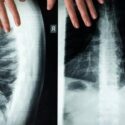

VA disability claims are evaluated using the Schedule for Rating Disabilities. Each condition is assigned a Diagnostic Code outlining criteria for various percentage levels. Ratings are based on functional impairment rather than diagnosis alone....